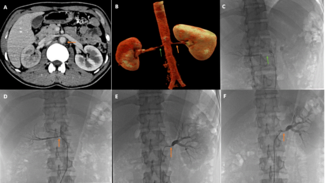

A 55-year-old man presented with medically controlled essential hypertension and a history of abdominal aortic aneurysm stenting 2 years prior who presented with a 3-month history of left lower extremity fatigue on exertion.